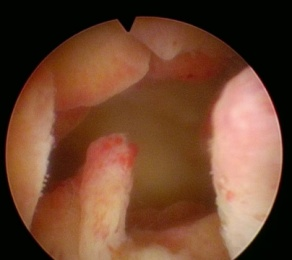

宫腔镜下的子宫内膜息肉

子宫内膜息肉像子宫内壁长出的“小肉赘”,多数为良性但可能影响生活。经期延长就像关不紧的水龙头,月经期间内裤上偶尔看到一点褐色或红色的血迹,量很少,时有时无。基于目前研究,估计育龄期、围绝经期及绝经后人群总体患病率为7.8%~34.9%。

(1) 宫腔镜检查

采用宫腔镜经过阴道及宫颈进入宫腔,查看宫腔内情况。这一方法可以明确诊断,排除恶性病变,而且经自然腔道给患者带来的创伤小。